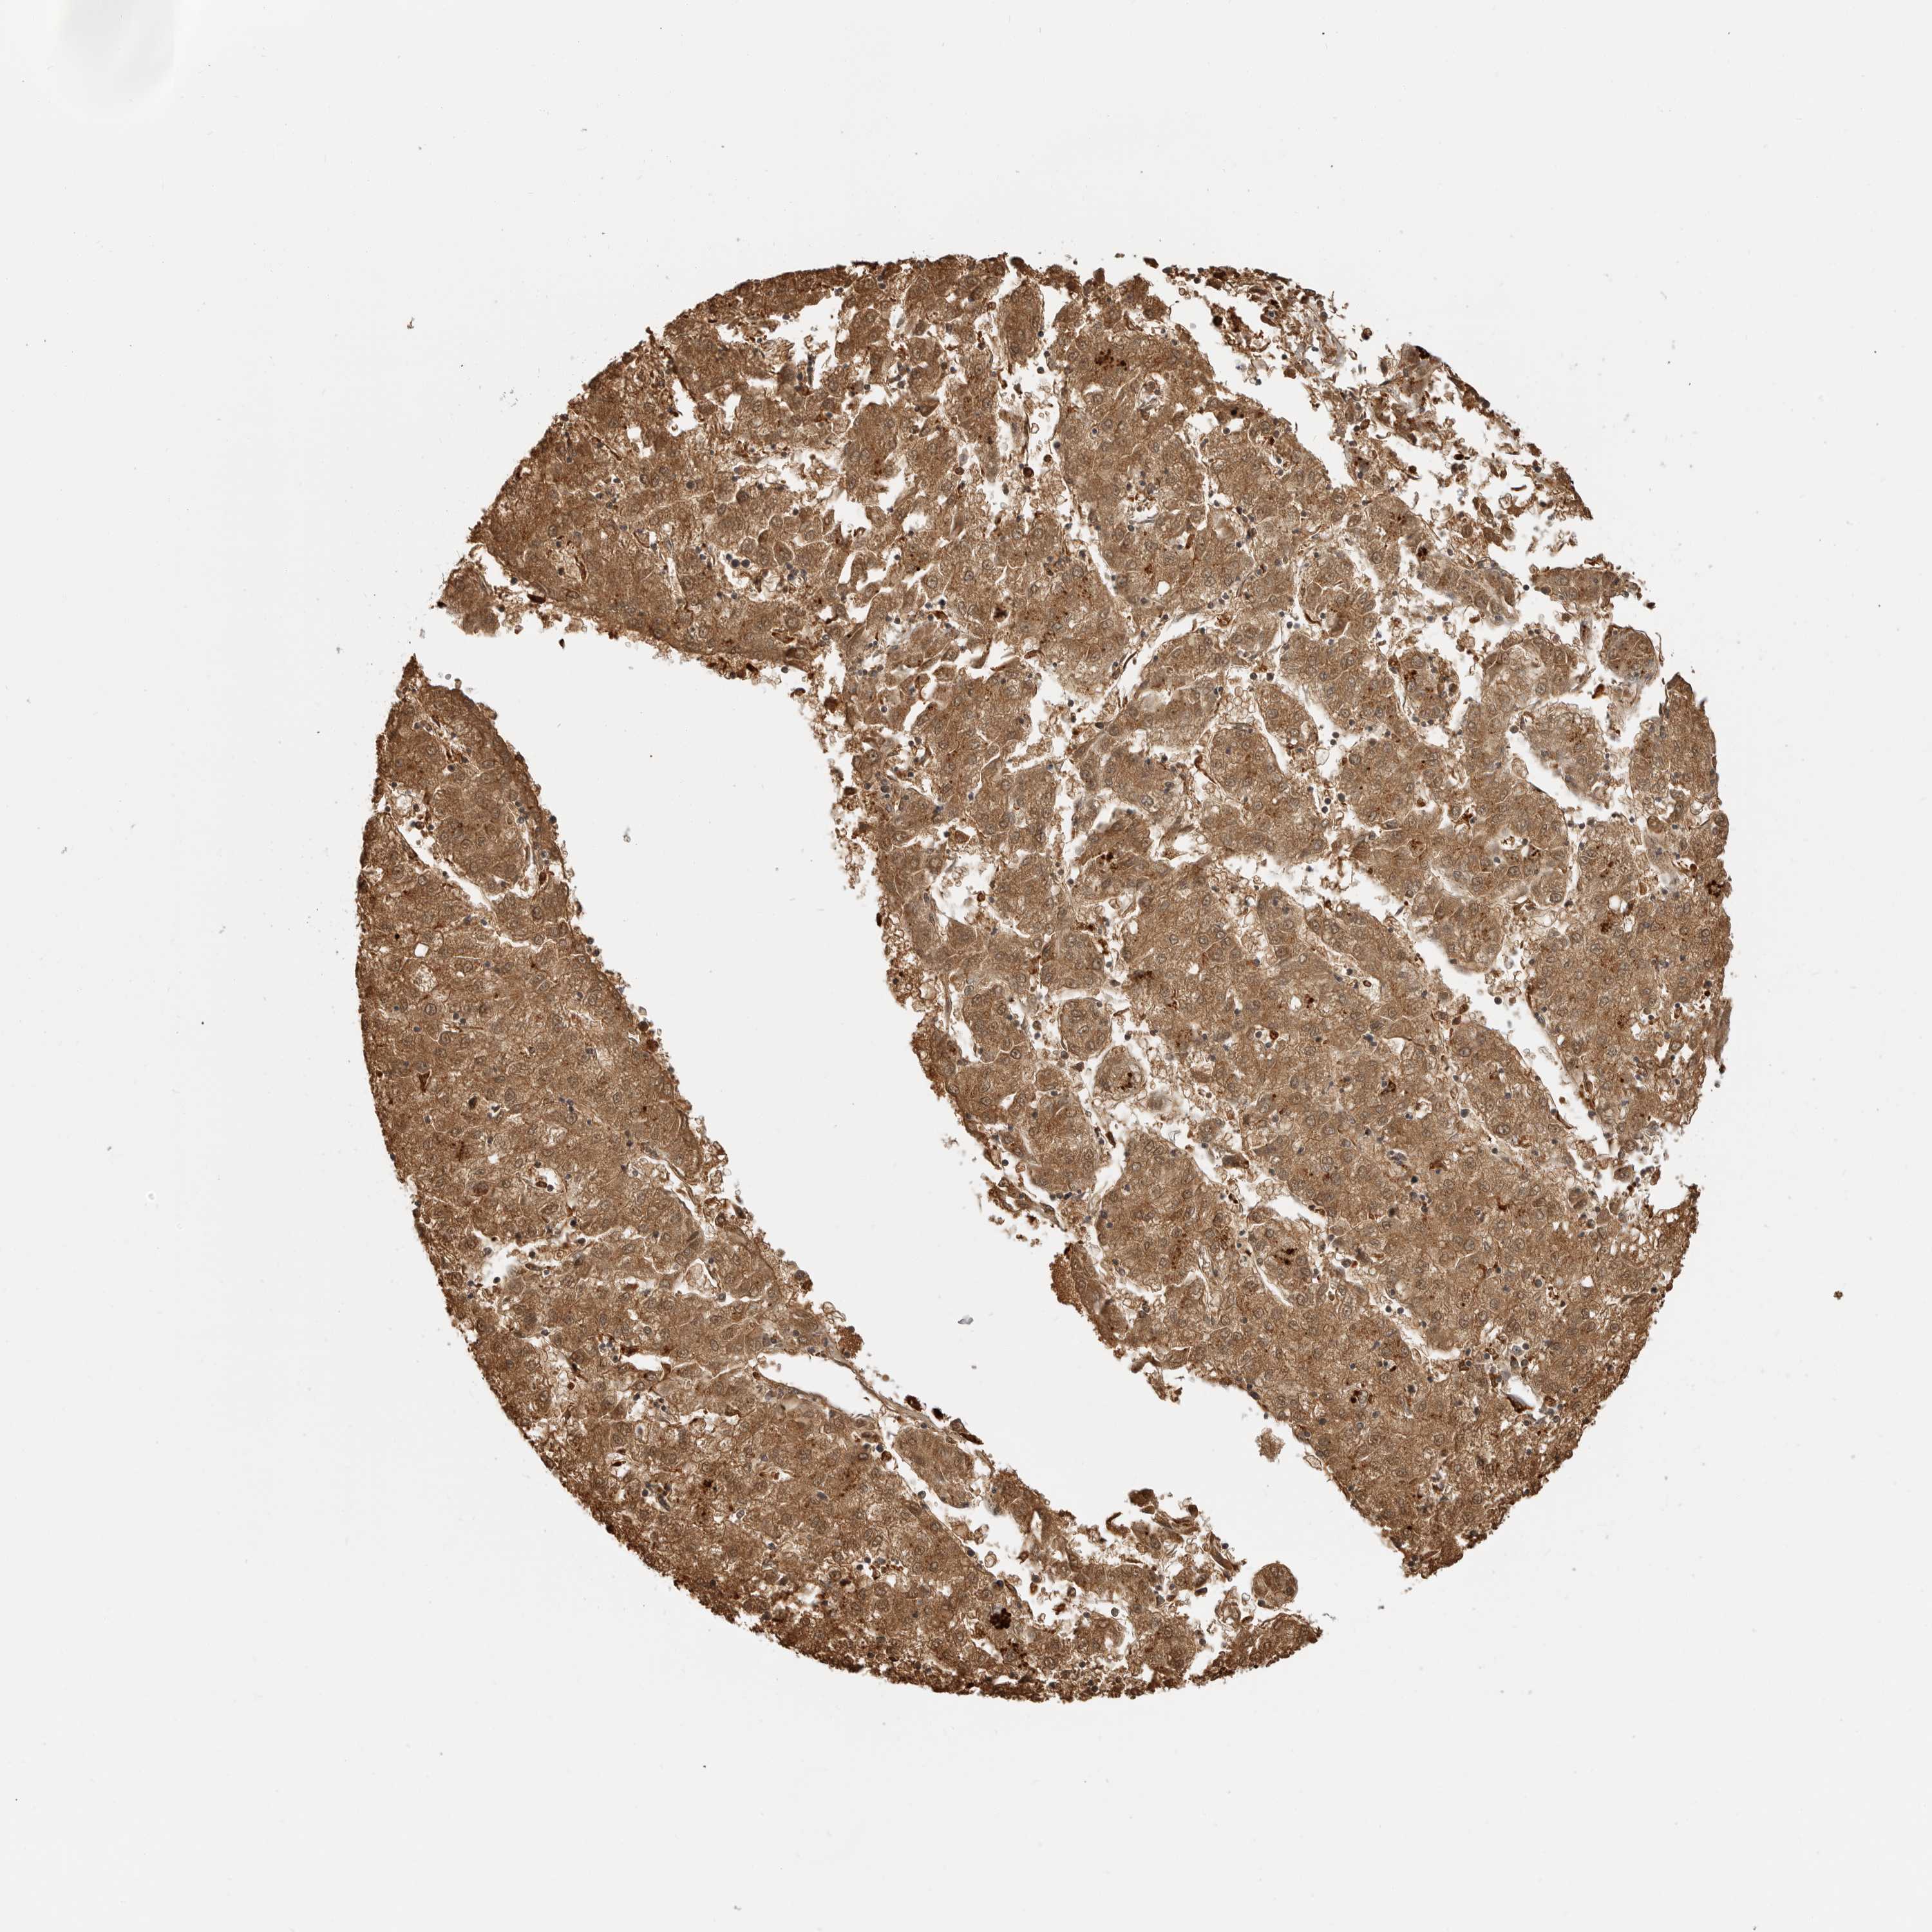

LIVER CANCER - Protein expressioni

A mouse-over function shows sample information and annotation data. Click on an image to view it in a full screen mode. Samples can be filtered based on level of antibody staining by selecting one or several of the following categories: high, medium, low and not detected. The assay and annotation is described here.

Note that samples used for immunohistochemistry by the Human Protein Atlas do not correspond to samples in the TCGA dataset.

Antibody stainingi

Antibody staining in the annotated cell types in the current human tissue is reported as not detected, low, medium, or high, based on conventional immunohistochemistry profiling in selected tissues. This score is based on the combination of the staining intensity and fraction of stained cells.

Each image is clickable and will lead to virtual microscopy that enables deeper exploration of all samples and also displays staining intensity scores, fraction scores and subcellular localization as well as patient and tissue information for each sample.

Antibody HPA026650

Staining

High

Medium

Low

Not detected

Intensity

Strong

Moderate

Weak

Negative

Quantity

>75%

75%-25%

<25%

None

Location

Nuclear

Cytoplasmic/membranous

Cytoplasmic/membranous,nuclear

Cholangiocarcinoma

Carcinoma, Hepatocellular, NOS